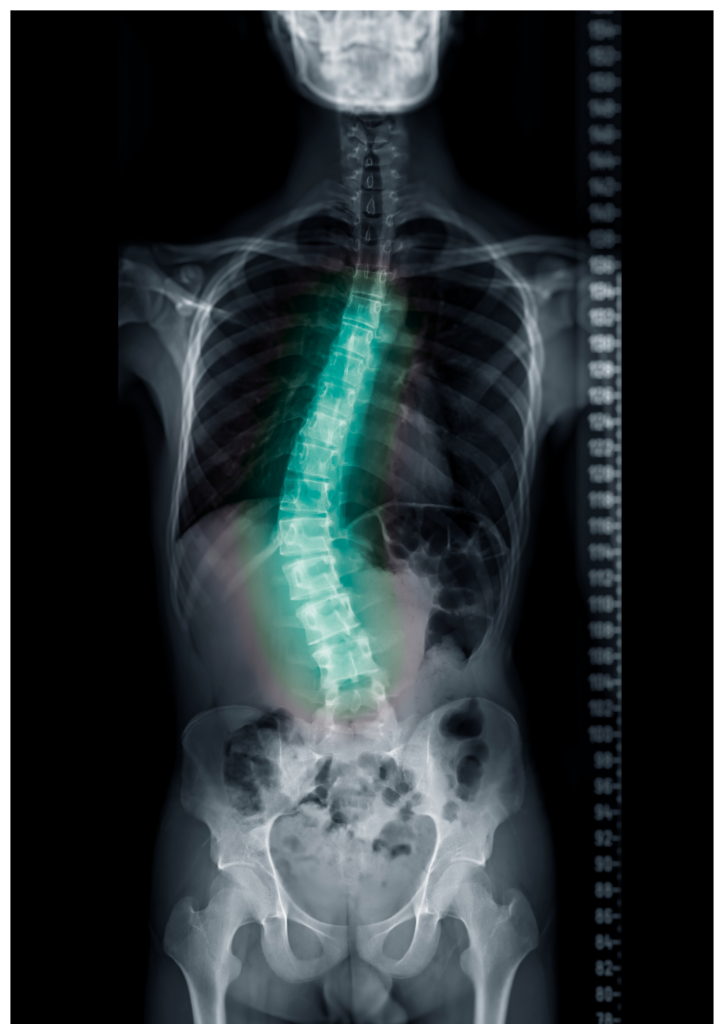

La scoliosi è una deviazione della colonna vertebrale che coinvolge anche una rotazione delle vertebre e significa che, non solo la schiena perde l’allineamento, ma cambia il modo in cui il corpo distribuisce i carichi durante la postura e il movimento.

La scoliosi può essere legata a squilibri muscolari, alterazioni posturali o differenze di carico tra i due lati del corpo. Non va interpretata solo come una “curva” ma come una condizione che coinvolte: colonna, bacino, respirazione e controllo motorio.